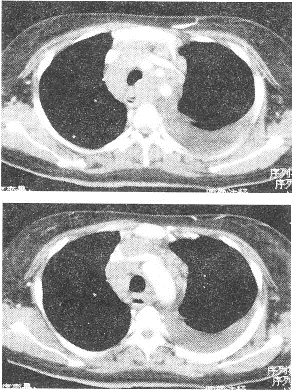

患者男性,咳嗽、咳痰6個月余,胸痛、乏力1個月。查體:左下肺呼吸音無。X線平片示:上縱隔影增寬,左側(cè)中量胸腔積液。胸部CT如圖所示:

正確答案:1.ADE;2.D;3.BC 解題思路:該例胸部CT可見縱隔淋巴結(jié)彌漫性淋巴結(jié)腫大.分布于血管周圍,最可能的是淋巴瘤。未治療的淋巴瘤較少出現(xiàn)壞死液化,增強掃描多為較均勻強化,這與淋巴結(jié)結(jié)核常為環(huán)形強化不同。